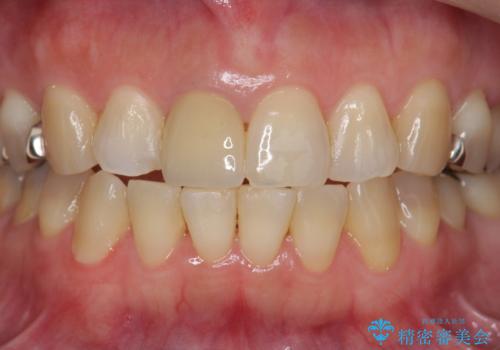

セラミッククラウン 歯ぐきの黒ずみの改善

- 十数年前に治療した前歯のクラウンの歯ぐきの位置が変化し、黒いラインが見え審美性の改善を求めて来院されました。

ファイバーコアのやりかえを行ったのち、金属を用いないジルコニアクラウンによる再補綴を行い前歯の審美性の向上を計画します。

近年前歯のクラウン製作に用いられるジルコニアクラウンは、金属を用いていないため経年的に歯ぐきの位置が変わっても黒いラインが見えることなく審美性の意地が期待できます。